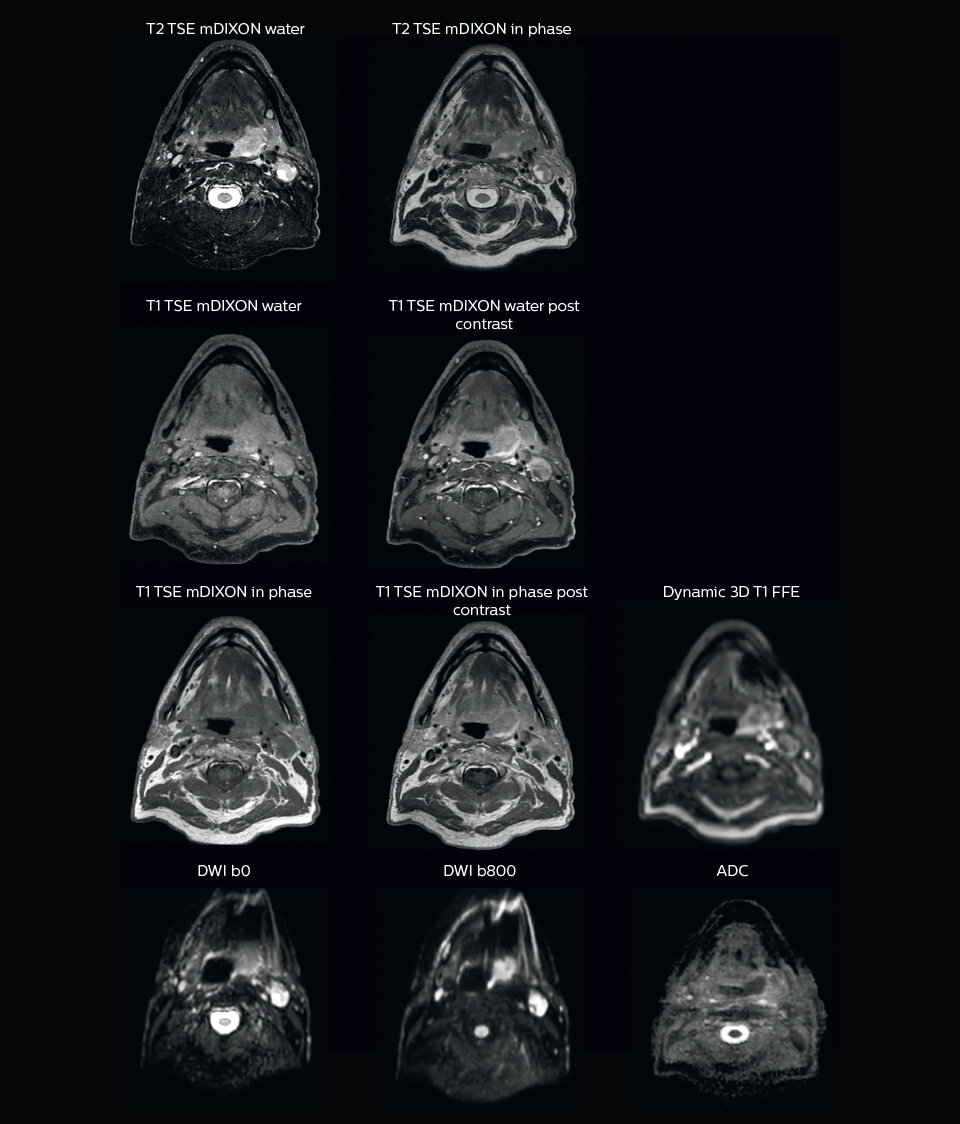

Visualizing critical structures with MRI before prostate radiation therapy

A 63-year-old patient with prostate cancer, cT3bNxM, Gleason 7, underwent MRI on Ingenia 3.0T MR-RT before radiation therapy.

Intraprostatic lesions are visible on the bTFE MR image, but not on the CT image. MRI shows excellent soft-tissue contrast for the visualization of critical structures like the rectum and penile bulb.

Fiducial markers (green arrows) are used in registration of MR images to CT, to transfer the MR-based delineations onto the CT image dataset.

“We use pre- and post-contrast T1- and T2-weighted sequences with the fast and robust mDIXON method for fat suppression,” says Dr. Philippens. “Dynamic contrast-enhanced imaging is performed with high temporal resolution and low spatial resolution, to see the contrast agent uptake in the tumor. Diffusion weighted imaging is used qualitatively to see how the tumor extends into another structure, rather than for strict delineation.”

“In postoperative patients who have had tumor growth along the cranial nerves, we use T2-weighted gradient echo (FFE) on our 3.0T MR-RT scanner to show the nerves for target delineation and look to see if there is still tumor left.”